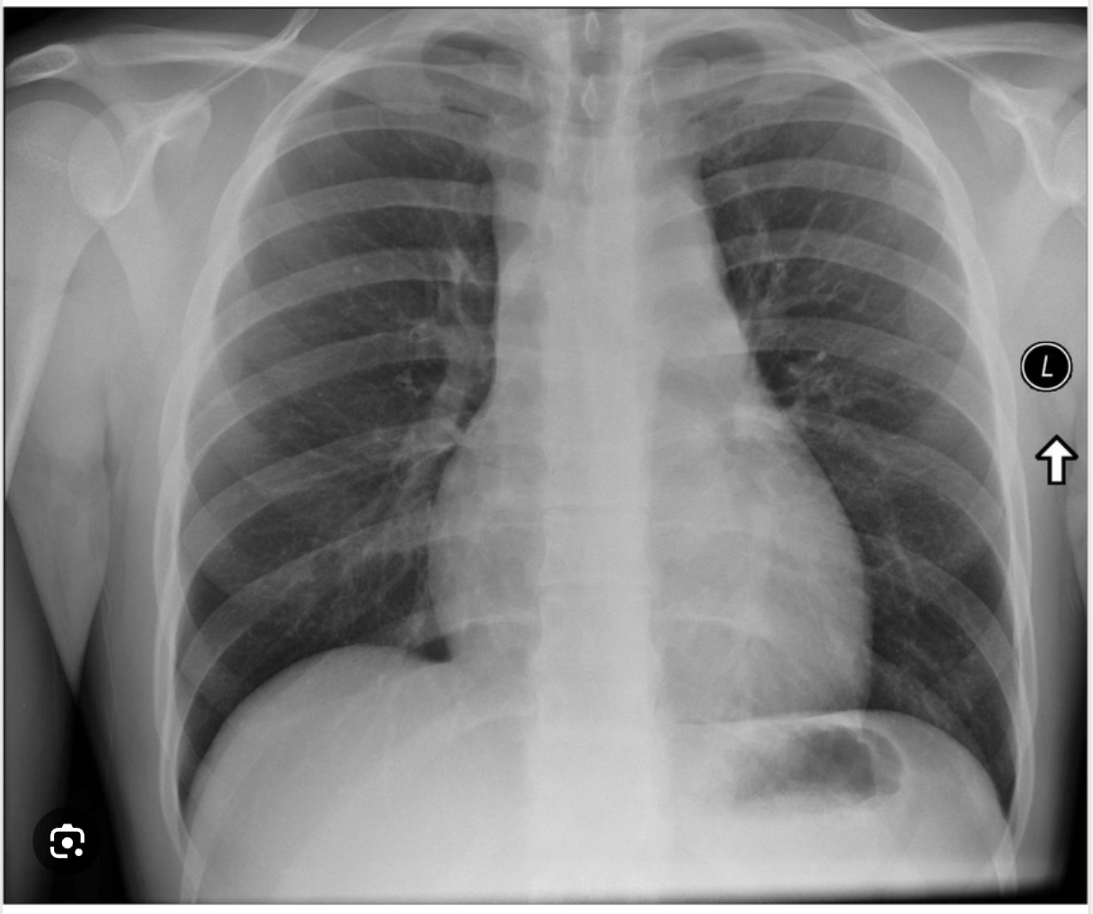

20/F with sudden onset chest pain. Cause?

Aortic dissection